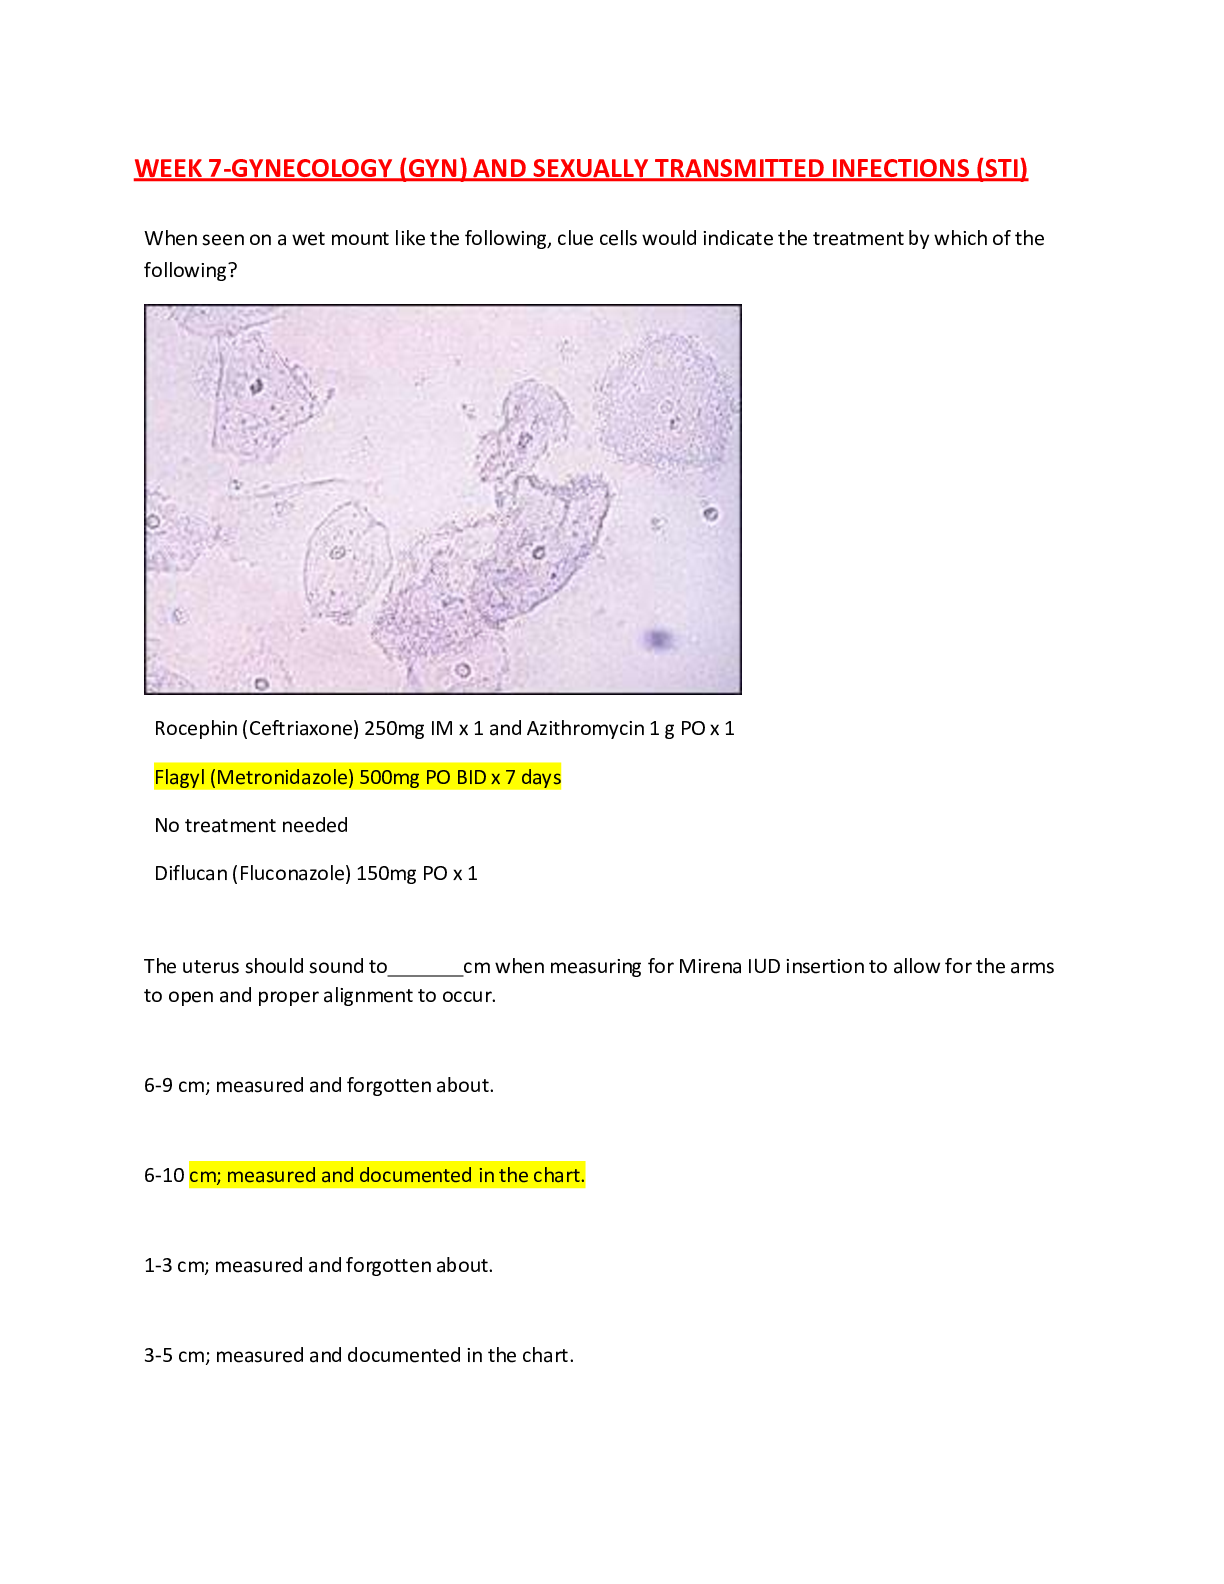

Preview image of WGU c170 THE MOST IMPORTANT SQL COMMANDS document